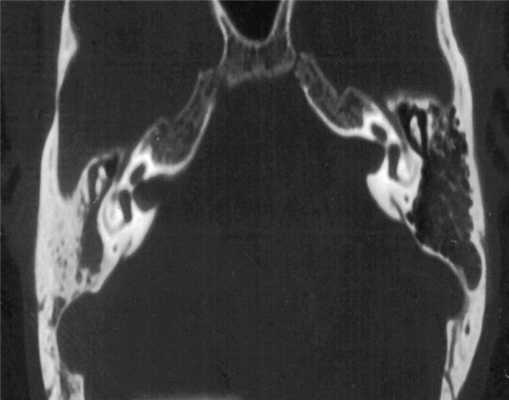

Пациентка Ф. обратилась с жалобами на снижение слуха на правое ухо, периодические выделения из правого уха. Жалобы беспокоят в течение 6 лет, лечилась консервативно. При отомикроскопии визуализируется перфорация в верхнем отделе барабанной перепонки. В предоперационном обследовании было выполнено КТ височных костей. Выявлено мягкотканное образование правого уха, заполняющее барабанную полость, адитус, антрум, склероз клеток сосцевидного отростка (рис. 1). Рисунок 1. КТ височных костей пациентки Ф. в аксиальной проекции.

В связи с наличием у пациентки хронического гнойного среднего отита с холестеатомой выполнена санирующая операция на правом ухе. Была выявлена холестеатома, заполняющая аттик, адитус, антрум, деструкция цепи слуховых косточек. Производилась облитерация паратимпанальных пространств с помощью остеокондуктивного биостекла (Биоситал), задняя стенка наружного слухового прохода восстанавливалась с помощью хондро-перихондральных фрагментов, также выполнялась тимпанопластика II типа (рис. 2, а, б на цв. вклейке). Рисунок 2. Вид операционного поля. а - послеоперационная полость заполнена гранулами Биоситала Рисунок 2. Вид операционного поля. б - задняя стенка наружного слухового прохода восстановлена с помощью хондро-перихондрального фрагмента.